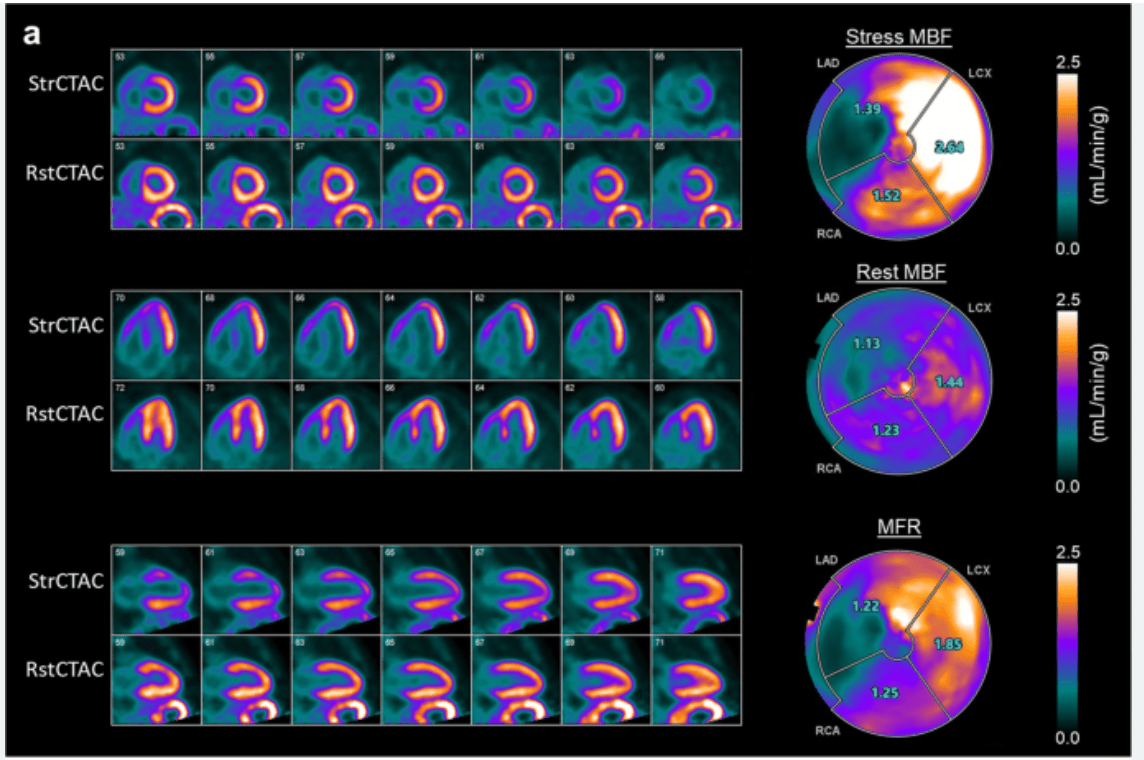

Spot diagnosis?

Microvascular dysfunction (MBFR<2)